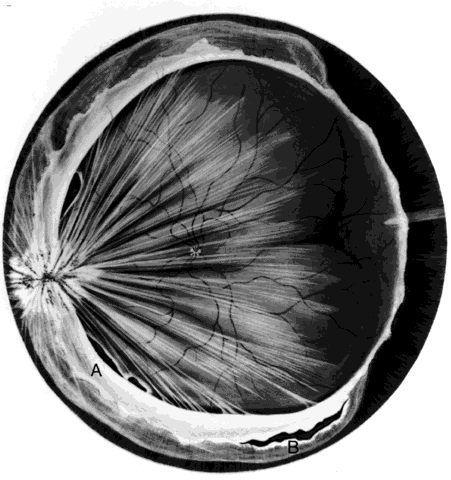

hemorrhage, retinal breaks, and retinal detachment. SUBLUXATION OR DISLOCATION OF THE LENS Minor degrees of subluxation should be suspected when phakodonesis or iridodonesis is noted. Zonular rupture is certain if there is vitreous prolapse into the anterior chamber. In the absence of cataractous changes and related visual impairment, treatment is not indicated. A subluxated, cataractous lens can be removed by aspiration-irrigation or phacofragmentation through a limbal incision, but complications may occur, including posterior dislocation of the lens or lens fragments, vitreous prolapse and incarceration, and vitreous aspiration with resultant vitreous base traction and retinal tear formation. Also, visualization of the anterior vitreous by coaxial illumination is poor compared with fiberoptic endoillumination. These problems make pars plana lensectomy an attractive alternative. Bimanual techniques permit fixation and simultaneous removal of the lens by the vitreous suction-cutter, if the lens is soft, or phacofragmentation if it is sclerotic (Fig. 1A). Posteriorly dislocated fragments can be removed safely, with minimal vitreous traction, using the same incisions and instruments (see Fig. 1B). With endoillumination, prolapsed and juxtalenticular vitreous is readily identified and excised with the vitrectomy probe. Without question, pars plana lensectomy is the preferred method for removing a completely dislocated lens. The technical aspects of dislocated lens and lens fragment removal are described elsewhere in these volumes. VITREOUS HEMORRHAGE Blood in the vitreous may come from tears in the iris, ciliary body, choroid, or retina. Hemorrhage from choroidal ruptures accumulates beneath the neurosensory retina; it then passes through the retina into the vitreous without necessarily causing a retinal break. Regardless, it is important to assume that a retinal break is present until proved otherwise. Vitrectomy is indicated for vitreous hemorrhage caused by ocular contusion when a retinal detachment is suspected because of sudden additional loss of vision, when a retinal detachment is detected through a window in the hemorrhage, when a large retinal break or retinal detachment is diagnosed by ultrasound, or when there is no improvement after a reasonable period of observation. Preoperative contact A-scan and B-scan ultrasonography is helpful for detecting posterior vitreous detachment and differentiating it from retinal detachment. It is dangerous, however, to rely completely upon the accuracy of ultrasound. The presumed posterior hyaloid should be approached with caution until it can be identified with certainty. A standard three-port vitrectomy technique is preferred for nonclearing vitreous hemorrhage. Initially, a central core of opaque vitreous is removed, beginning sufficiently close to the lens that the tips of the cutter and endoilluminator can be visualized. The excision is carried posteriorly, removing successive layers of hemorrhagic and fibrinous vitreous, until the anticipated plane of the posterior hyaloid is approached. A constant surveillance is maintained for a gray membrane containing radially oriented vessels (undiagnosed detached retina). A small opening is made in the detached posterior hyaloid, through which unclotted blood is aspirated by use of active suction from a soft-tipped cannula. Once the retina has been visualized, it is best to remove as much retrohyaloid blood as possible to prevent dispersion into the vitreous cavity with consequent loss of visual control. If the posterior vitreous cortex is not detached, it can be separated from the retina by gentle suction with a soft-tipped cannula at the edge of the optic disc. The elevated cortex is penetrated with a hooked needle or myringotomy blade, creating a window through which a pick is introduced to enlarge the area of cleavage. With the plane between hyaloid and retina established, the surgeon attempts to remove the entire cortical vitreous except for the firmly attached portion at the anterior vitreous base. Cortex that does not separate with gentle manipulation is isolated from surrounding vitreous to eliminate traction on the retina. It is important to remove the cortical vitreous from areas adjacent to retinal breaks. Failure to do so may result in subsequent tangential traction and retinal detachment. A scleral buckle should be considered if retinal breaks cannot be freed from surrounding vitreous cortex. The placement of sclerotomies close to the 3 o'clock and 9 o'clock positions facilitates maximal excision of the hemorrhagic anterior vitreous skirt, thereby improving visualization of the peripheral retina and pars plana. With use of coaxial illumination and scleral depression, the peripheral vitreous on the temporal side of the globe is trimmed with the cutter placed in the temporal sclerotomy, reaching both the superior and inferior quadrants, after which it is transferred to the nasal sclerotomy, and the process is repeated. The fiberoptic endoilluminator may damage the lens if used internally to illuminate the peripheral vitreous on the opposite side of the globe. However, the cone of light from the probe may be directed through the cornea to augment or replace the coaxial light source. Hemorrhagic retrolenticular vitreous can be stripped from the posterior capsule of the lens by gentle aspiration into the cutting port followed by withdrawal of the probe and simultaneous activation of the cutting mode. This technique is dangerous in young children because the retrolenticular vitreous is adherent to the lens, which is sufficiently pliable for aspiration into the port with consequent cataract formation. When the lens is clear, the process of removing peripheral and retrolenticular vitreous is less important than preserving lens integrity in most cases. It is important to expose the peripheral retina and vitreous base because most retinal breaks caused by ocular contusion are located in this area.2 All retinal breaks should be treated. Endolaser is used for posterior breaks, whereas peripheral breaks are treated with indirect laser assisted by scleral depression or transscleral cryoretinopexy. Cryotherapy is preferred when residual opaque vitreous partially obscures the targeted break. Encircling scleral buckles are not necessary after vitrectomy for nonclearing vitreous hemorrhage caused by ocular contusion when a clear view of the fundus periphery reveals no peripheral retinal tears or signs of traction, such as vitreous base avulsion. Similarly, the support of a buckle is usually not needed for treated retinal breaks without retinal detachment. A local scleral buckle should be used when there is residual traction on a posterior break. The peripheral retina should be supported by an encircling scleral buckle when traction on breaks in the oral zone persists or the periphery is poorly visualized because of residual opaque vitreous. RETINAL BREAKS Retinal breaks are created at the time of nonpenetrating blunt injuries3 in 10% to 20% of eyes.3–6 Retinal dialyses are most frequent2–6 and are most often found in the lower temporal (Fig. 2) and upper nasal periphery (Fig. 3).2 Large irregular breaks at the point of impact of blunt trauma are less common but are equally characteristic of nonpenetrating injuries (see Fig. 3).2,7,8 Horseshoe and opercular tears of the equatorial retina (see Fig. 3) are associated with the more characteristic breaks in 25% of eyes.2 Small round holes in atrophic retina at the point of traumatic impact and macular holes (see Fig. 3) are infrequently observed after ocular contusion.2,8 Prophylactic treatment of most traumatic retinal breaks is indicated. Breaks at the point of impact are one exception because they are frequently self-sealing. The surrounding necrotic retina and choroid often unite in a common scar without prophylaxis. It is wise, however, to treat these large tears when scleral depression reveals a slight elevation and movement of their edges and the surrounding retina. Traumatic macular holes also are not treated to prevent additional loss of central vision. They seldom cause retinal detachments when left alone. RETINAL DETACHMENT Although retinal breaks are produced at the time of injury, the retinal detachment may be delayed for months to years because the vitreous gel acts like a tamponade until liquefaction occurs.2 The detachment is typically shallow and slowly progressive because the large volume of vitreous gel in younger eyes prevents bullous retinal elevation as commonly seen in older patients with nontraumatic retinal detachments. Careful preoperative and intraoperative indirect ophthalmoscopy with scleral depression is the key to successful treatment of detachments caused by traumatic retinal dialyses. Small dialyses at the vitreous base borders are difficult to identify, particularly in the upper nasal quadrant where they frequently occur. Breaks of the pars plana epithelium, at the anterior vitreous base border, are less apparent than retinal tears at the posterior edge of the vitreous base. Small dialyses are closed by scleral depression, in which case they are more easily seen on the lateral slopes of the indentation than on its crest. Transscleral cryotherapy is diagnostically helpful. It is not unusual to discover breaks at the vitreous base border for the first time when the edges of the tear are whitened by freezing a suspicious area. It is prudent to treat the entire zone of vitreous base pathology with cryotherapy under direct visual control (see Fig. 3). In this way, treatment of all retinal breaks is assured. The anterior, posterior, and lateral limits of the treated zone are carefully localized and supported by a broad scleral buckle to relieve traction on the entire area. The posterior edge of the dialysis should fall on the crest of the buckle, which must be sufficiently broad to support the anterior edge as well, thereby preventing a recurrent detachment due to anterior leakage. Segments of grooved solid silicone tires are used together with an encircling band, which is positioned on a great circle of the globe to minimize anterior or posterior migration of the buckle. The band is tightened to ensure permanent indentation of the tire segment, but a high encircling buckle is avoided because it promotes posterior gaping or “fish-mouthing” of the dialysis. The band is anchored by a nonabsorbable mattress suture or scleral belt loop in each of the quadrants not occupied by the tire segment. The retinal detachment is often shallow. To avoid retinal perforation or incarceration, subretinal fluid is released through a sclerotomy in an area of sufficient retinal elevation determined by intraoperative indirect ophthalmoscopy with scleral depression. Viewed in profile, the scleral indentation helps gauge the distance between retina and retinal pigment epithelium. To avoid retinal incarceration and blowout, sclerotomies posterior to the buckle should be securely closed after the release of fluid, particularly if additional manipulation of the buckle or an intravitreal gas injection is anticipated. Retinal dialyses in the lower temporal quadrant are often very large, with gaping posterior edges located well behind the equator (see Fig. 2). They are caused by injuries impacting the lower temporal portion of the globe that result in the dissolution and disappearance of retinal tissue.8 In contrast to nontraumatic giant retinal tears with rolled-over retina, they respond favorably to scleral buckling without vitrectomy. A scleral buckle is indicated for smaller dialyses that can be closed with an explant of reasonable size. Very large breaks, as illustrated in Figure 2, are best treated with vitrectomy, gas tamponade, and laser, as recommended for nontraumatic giant retinal tears, rather than with a very large scleral buckle. Traumatic horseshoe and opercular tears are treated with scleral buckling surgery, as are similar nontraumatic retinal breaks. Likewise, traumatic macular holes in detached retina are managed by vitrectomy, internal drainage, and gas tamponade. The use of laser in such cases is controversial but is probably indicated for recurrent detachments and eyes with pre-existing poor central vision due to other traumatic macular damage. |